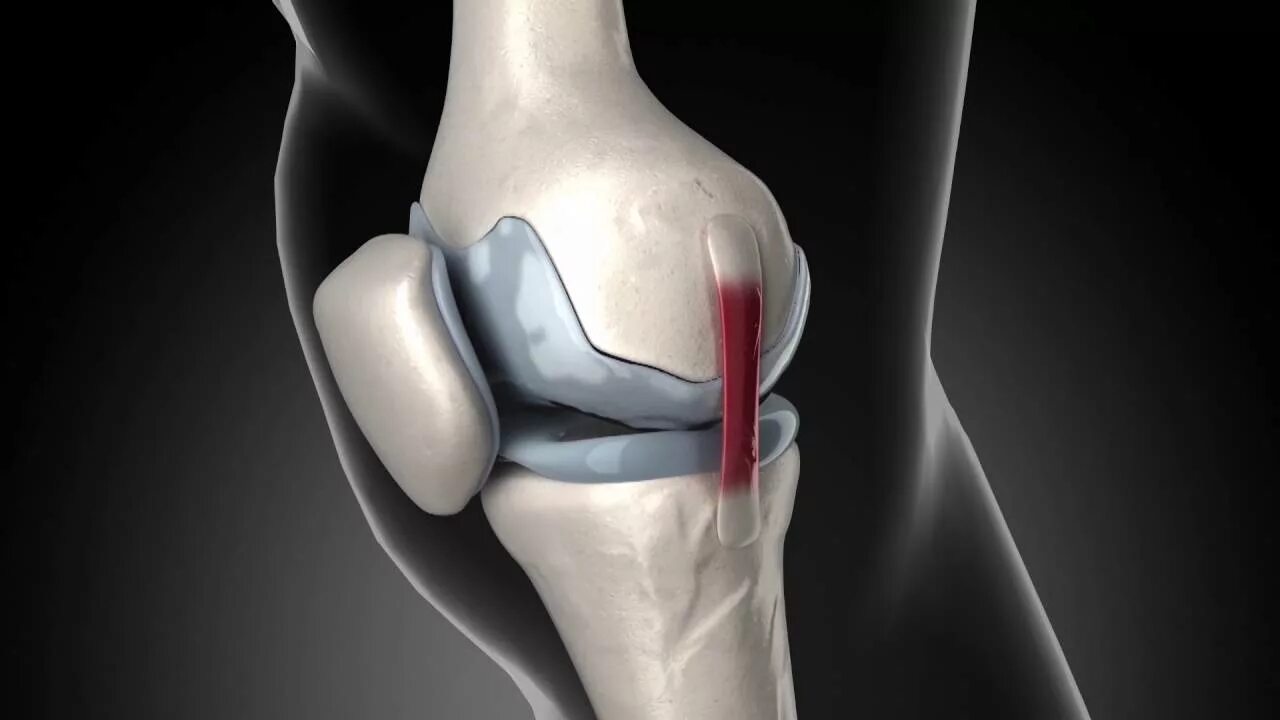

Артрит операции